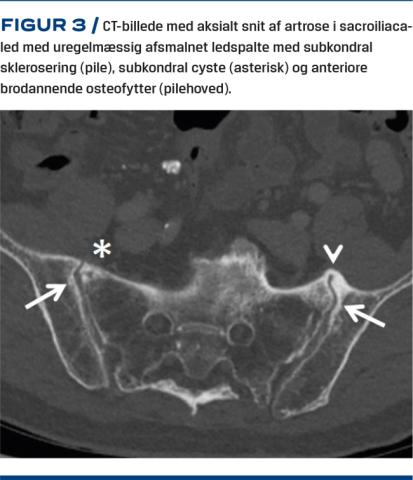

I facetledsartrose indgår både degenerative og proliferative elementer herunder ledspalteafsmalning, subartikulær knoglerosion, subkondrale cyster og osteofytter [17]. I lænden visualiseres facetleddene bedst ved skråoptagelser pga. facetleddenes orientering, dog kan man ved skråoptagelsen kun skelne mellem tilstedeværelse og fravær af facetledsartrose [13]. Laterale optagelser bør tages med patienten stående for at visualisere eventuel instabilitet og sagittalbalance (Figur 1). Med CT demonstreres facetleddene i sekventielle tværsnit med mulighed for supplerende tredimensionelle rekonstruktioner, hvilket optimerer visualiseringen af morfologien og eventuelle strukturelle forandringer af leddet. På trods af at CT er bedre end MR-skanning til vurdering af knoglepatologi, er der moderat til god overensstemmelse mellem resultaterne af de to undersøgelsestyper [18].

Ved røntgenoptagelse af bækkenet/SI-led kan man påvise sværere grader af artrose i form af osteofytter, sklerosering og ledspalteafsmalning. Pga. leddets lejring er undersøgelsen ikke sensitiv for lettere forandringer. Ved CT påvises der fokal irregulær ledspalteafsmalning, marginale osteofytter, subkondral sklerosering, cystedannelse og vakuumfænomener (Figur 3). Der observeres samme grad af artrose hos patienter med kroniske SI-ledsmerter og raske kontrolpersoner, og CT er ikke valideret til identifikation af symptomatisk SI-ledsartrose [21]. Ved MR-skanning kan man ligesom ved CT påvise uregelmæssig ledspalteafsmalning, osteofytter og forskellige grader af sklerosering [22]. Subkondral eller periartikulær knoglemarvsødem er et hyppigt fund hos patienter, der har kroniske uspecifikke rygsmerter på degenerativ basis [23]. Degenerative forandringer ses hos både aymptomatiske patienter og patienter med kroniske rygsmerter og kan ikke stå alene uden en klinisk vurdering.